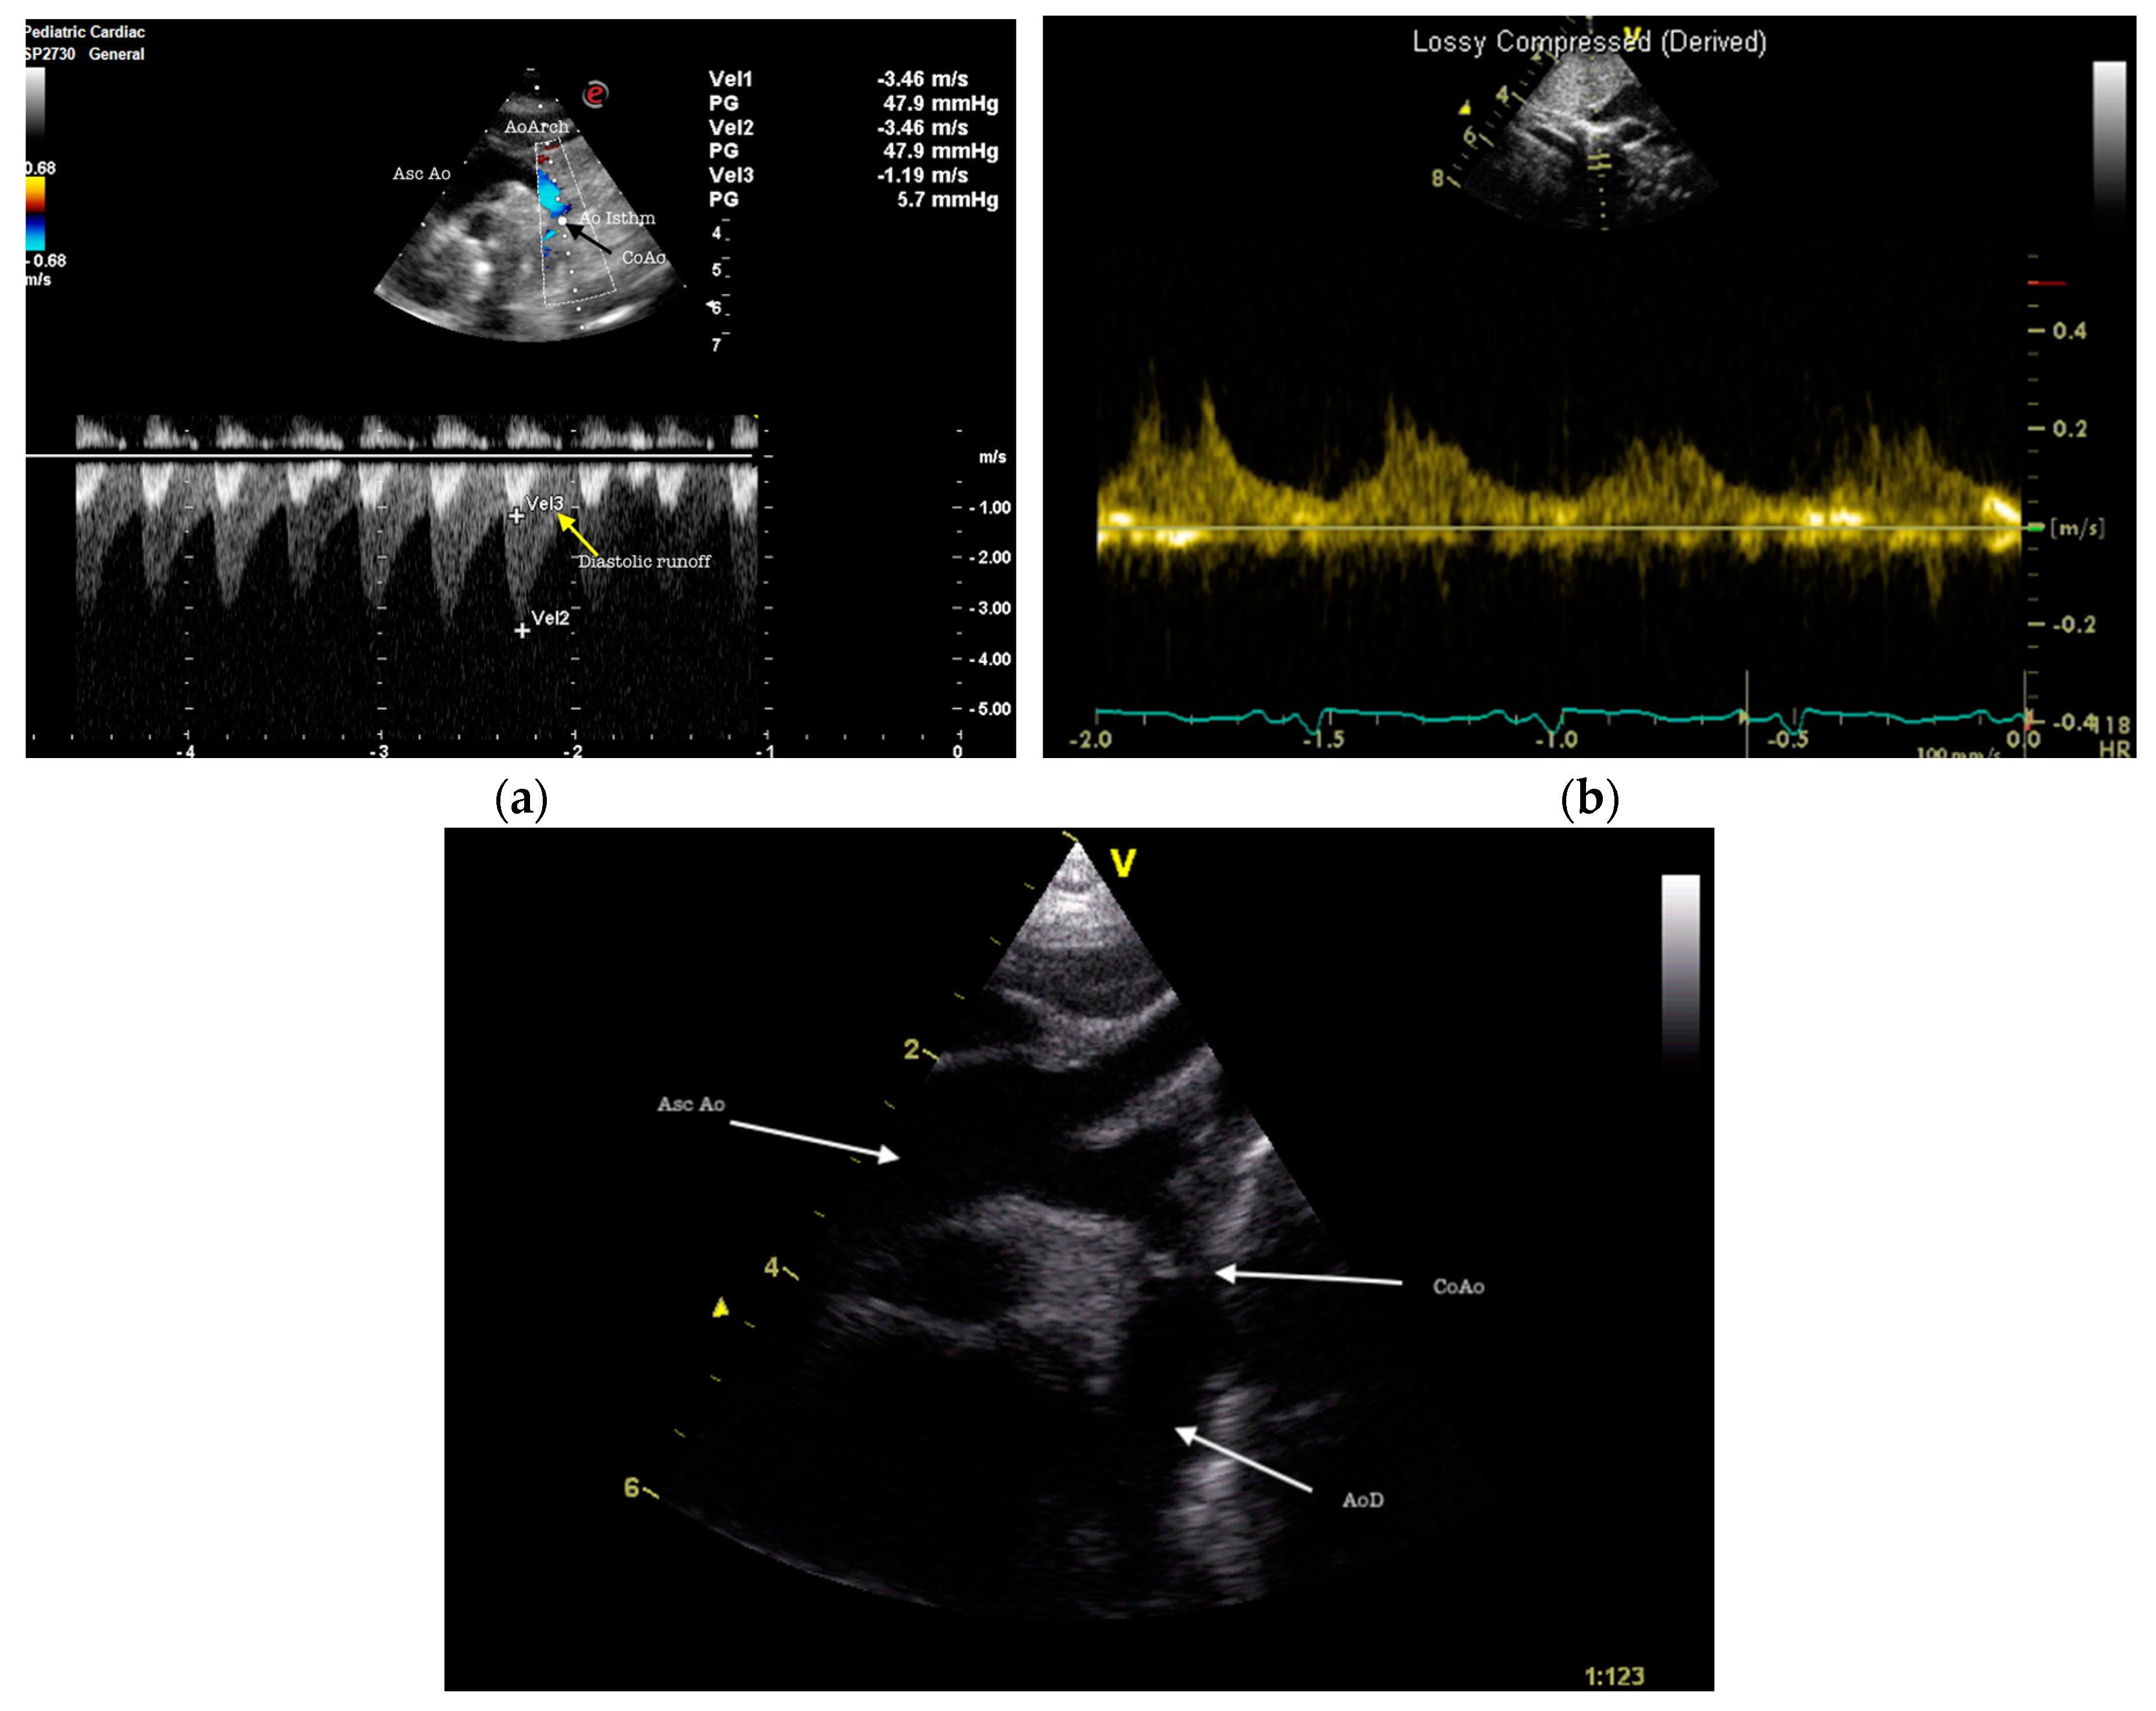

Figure 4. Coarctation of the aorta. (a) suprasternal view in transthoracic echocardiography showing flow velocity acceleration with diastolic runoff (yellow arrows) in the distal 5th aortic arch. AscAo, ascending aorta; AoArch, aortic arch; Ao isthm, aortic isthmus, CoAo, aorctation of aorta; (b) subcostal view in transthoracic echocardiography showing reduced flow velocity at the abdominal aorta level with a diastolic “tail” consistent with severe coarctation of aorta with reduced pulse width; (c) suprasternal long axis view showing significant preductal coarctation. There is a calibre discrepancy between the Asc Ao and transverse arch. Asc Ao, ascending aorta; CoAo, coarctation of aorta; AoD, descending aorta.